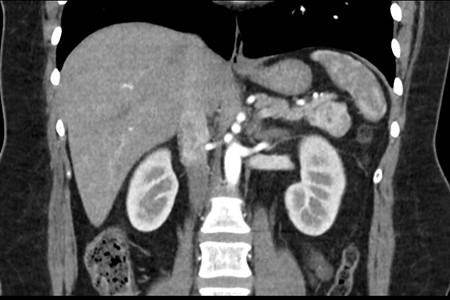

Caso 4

Paciente masculino de 35 años de edad, con antecedentes de tabaquismo, etilismo, consumo de sustancias psicoactivas. Ingresa al hospital de Sanatorio Franchin el 24 de mayo de 2024, donde se constata hipoglucemia severa con buena respuesta al glucosado hipertónico endovenoso. Al examen físico con la típica tríada de Whipple, dado por síntomas neuroglucopénicos de alteración del estado de conciencia, glucemia de 25 mg/dl y alivio sintomático después de la administración de glucosa. El paciente recupera el estado de conciencia y refiere dolor abdominal a nivel de epigastrio, por lo que se le realiza ecografía abdominal, donde se evidencia lesión nodular hipoecogénica en cuerpo del páncreas. Por esta razón se pasa al paciente a tomografía, donde se constata una formación nodular a nivel del cuerpo del páncreas, que presenta un ávido realce en fase arterial con homogeneización de la lesión en tiempo tardío.

Ahora bien, como se mencionaba al principio, el estudio ecográfico es de muy baja sensibilidad y se identifique o no la lesión por este estudio, nuestro siguiente paso en el algoritmo diagnóstico de esta lesión es la tomografía. Esta es la prueba no invasiva inicial, con una sensibilidad del 63% al 83%, y detecta del 70% al 80% de los tumores. Esta debe realizarse como un estudio trifásico: fase arterial temprana a los 30 segundos, fase venosa a los 70 segundos, fase tardía de 3 a 5 minutos. La característica de estos tumores por tomografía es que se presentan como una masa sólida que tiene un ávido realce en la fase arterial, cuyo realce se mantiene y se observa más tenue en la fase venosa y en los tiempos tardíos la lesión se homogeniza.

Para mi caso, y dando una visión general de los métodos de imagen no invasivos en esta revisión retrospectiva, solo a uno de los pacientes se le detectó la lesión por ecografía, donde se visualizó una lesión nodular hipoecogénica en el cuerpo del páncreas. A los demás pacientes se les detectó la lesión por tomografía en estudio trifásico, donde resaltan las características ya descritas por la literatura de lesiones hipervasculares con intenso realce en fase arterial, localizadas en diferentes partes del páncreas, como cabeza, cuerpo y cola.